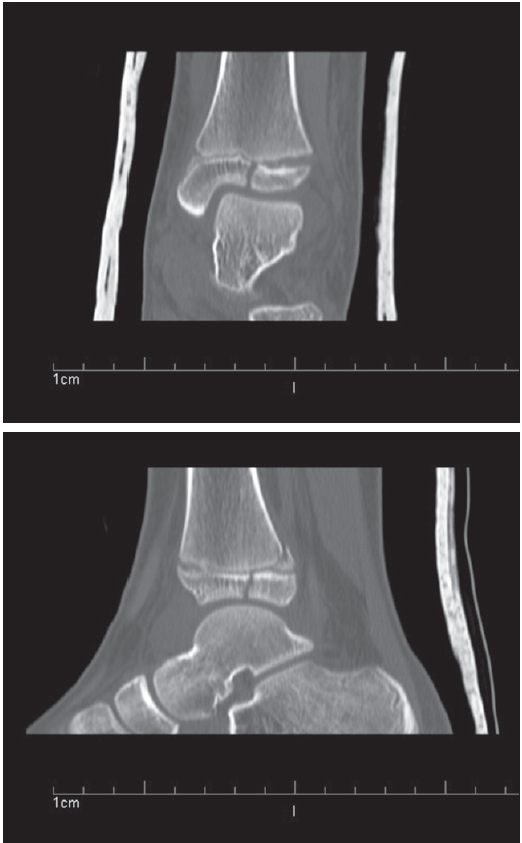

The radiographs showed a Salter-Harris IV fracture. CT scans confirmed the presence of a triplane fracture of the distal tibial epiphysis (Figure).

As in this case, a plain radiograph will show a Salter-Harris II fracture on the lateral view and a Salter-Harris III fracture on the anteroposterior view. CT is needed to clearly delineate the fracture planes and segments.4,5